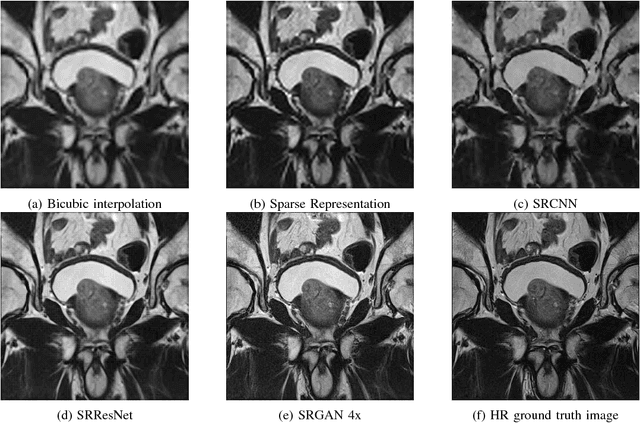

Abstract:Acquiring High Resolution (HR) Magnetic Resonance (MR) images requires the patient to remain still for long periods of time, which causes patient discomfort and increases the probability of motion induced image artifacts. A possible solution is to acquire low resolution (LR) images and to process them with the Super Resolution Generative Adversarial Network (SRGAN) to create an HR version. Acquiring LR images requires a lower scan time than acquiring HR images, which allows for higher patient comfort and scanner throughput. This work applies SRGAN to MR images of the prostate to improve the in-plane resolution by factors of 4 and 8. The term 'super resolution' in the context of this paper defines the post processing enhancement of medical images as opposed to 'high resolution' which defines native image resolution acquired during the MR acquisition phase. We also compare the SRGAN to three other models: SRCNN, SRResNet, and Sparse Representation. While the SRGAN results do not have the best Peak Signal to Noise Ratio (PSNR) or Structural Similarity (SSIM) metrics, they are the visually most similar to the original HR images, as portrayed by the Mean Opinion Score (MOS) results.

Abstract:Acquiring High Resolution (HR) Magnetic Resonance (MR) images requires the patient to remain still for long periods of time, which causes patient discomfort and increases the probability of motion induced image artifacts. A possible solution is to acquire low resolution (LR) images and to process them with the Super Resolution Generative Adversarial Network (SRGAN) to create a super-resolved version. This work applies SRGAN to MR images of the prostate and performs three experiments. The first experiment explores improving the in-plane MR image resolution by factors of 4 and 8, and shows that, while the PSNR and SSIM (Structural SIMilarity) metrics are lower than the isotropic bicubic interpolation baseline, the SRGAN is able to create images that have high edge fidelity. The second experiment explores anisotropic super-resolution via synthetic images, in that the input images to the network are anisotropically downsampled versions of HR images. This experiment demonstrates the ability of the modified SRGAN to perform anisotropic super-resolution, with quantitative image metrics that are comparable to those of the anisotropic bicubic interpolation baseline. Finally, the third experiment applies a modified version of the SRGAN to super-resolve anisotropic images obtained from the through-plane slices of the volumetric MR data. The output super-resolved images contain a significant amount of high frequency information that make them visually close to their HR counterparts. Overall, the promising results from each experiment show that super-resolution for MR images is a successful technique and that producing isotropic MR image volumes from anisotropic slices is an achievable goal.